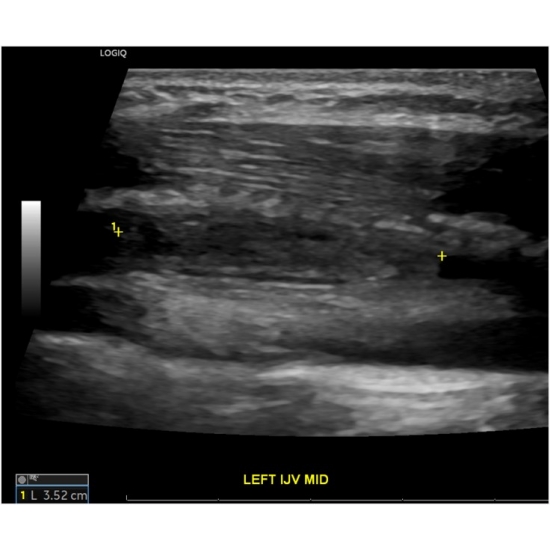

Given her significant neck swelling, ED providers ordered venous doppler ultrasound of the upper extremities.

Venous Doppler of the Upper Extremity bilateral: Occlusive thrombus within the left internal jugular vein measuring approximately 3.1 cm length. Case Photo #10 , Case Photo #2 and Case Photo #3